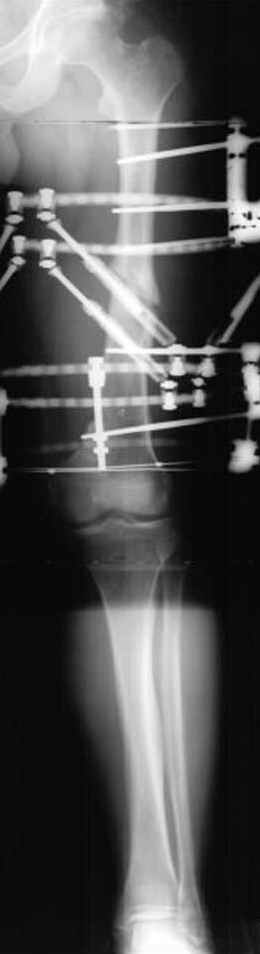

Если, например, доводится лечить больных с псевдартрозами шейки бедра, то надобность есть, и приходится. См. приложение.

Несколько снимков из моей коллекции, чтобы разьяснить, почему мы до сих пор делаем различные варианты остеотомии.

На рисунке N1 предоперационный план лечения ложного сустава шейки бедра- линия ложного сустава, угол и направление введения импланта, клиновидная остеотомия в градусах и миллиметрах, второй снимок после коррекции, расчет, на сколько удлиняется конечность и размеры импланта;

N3 рисунок окончательный снимок, после операции моя рентгенограмма должен выглядеть примерно как эта картина. На N4 снимке клин перед удалением; N5 послеоперации 3 нед.; N6 окончательная рентгенограмма.

Отправитель: Djoldas Kuldjanov 23 Ноябрь 2004, 18:21

пластическая модель; и коррекция бедра аппаратом Илизарова.